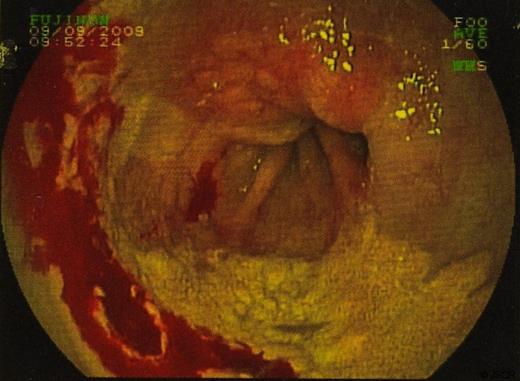

In September 2009 the patient underwent a colonoscopy and oesophagogastroduodenoscopy (OGD). Colonoscopy was unremarkable. However, views of the oesophagus on OGD showed what was thought to be a superficially spreading tumour, 35cm from the incisors and 5 cms in length. Barrett’s oesophagus was also seen. (figure 1 & 2)